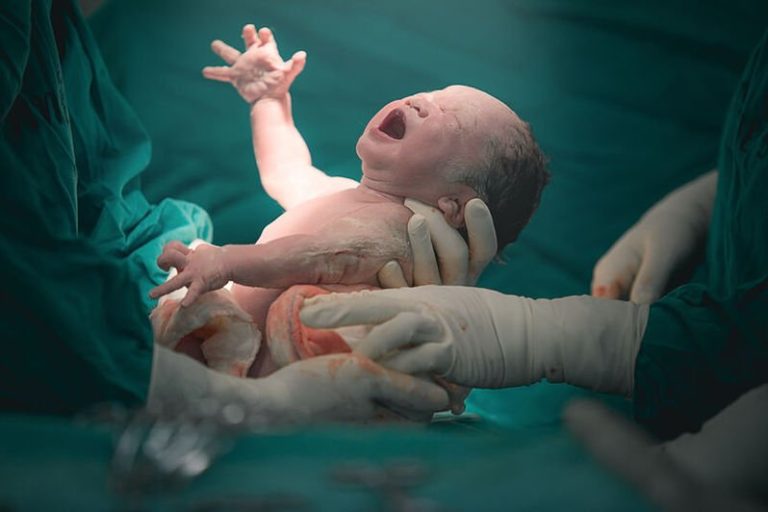

Со особена чест и задоволство ве известуваме дека повторно ја возобновуваме школата за психофизичка подготовка на трудници на ЈЗУ Универзитетска клиника за гинекологија и акушерство, како и можноста за безболно породување. Се во врска со Школата за трудници низ интервјуто со проф. д-р Ирена Алексиоска Папестиев, директорка на Универзитетската клиника за гинекологија и акушерство. СЛЕДЕТЕ…